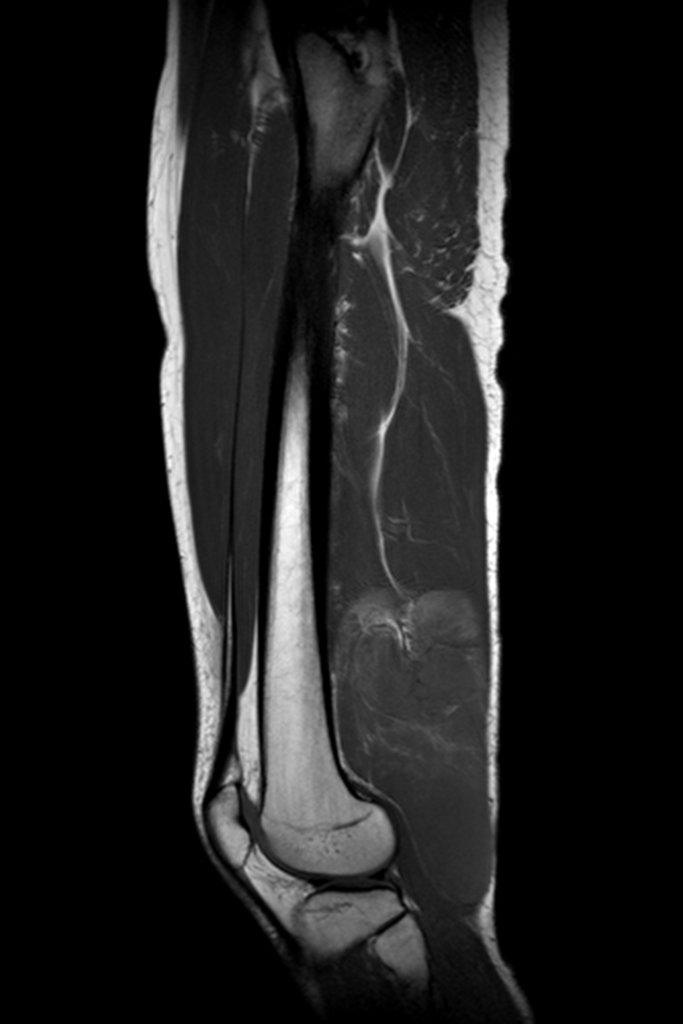

Liposarcoma mixoide. Paciente masculino, 28 años, refiere dolor y abultamiento progresivo en región posterior del muslo derecho, en sentido distal, desde hace 8 meses, niega traumatismo local. Inicialmente buscó un servicio de ortopedia, le realizaron una biopsia y le diagnosticaron liposarcoma mixoide.

Derivado a nuestro servicio encontramos una tumoración extensa en la superficie posterior del muslo, desde el tercio medio hasta la línea articular, sin dolor ni déficit neurológico.

Las imágenes por resonancia magnética, figuras 1 a 14, demuestran la heterogeneidad de la lesión y su agresividad, mostrando la gran extensión de la lesión y su proximidad al haz vascular-nervioso.